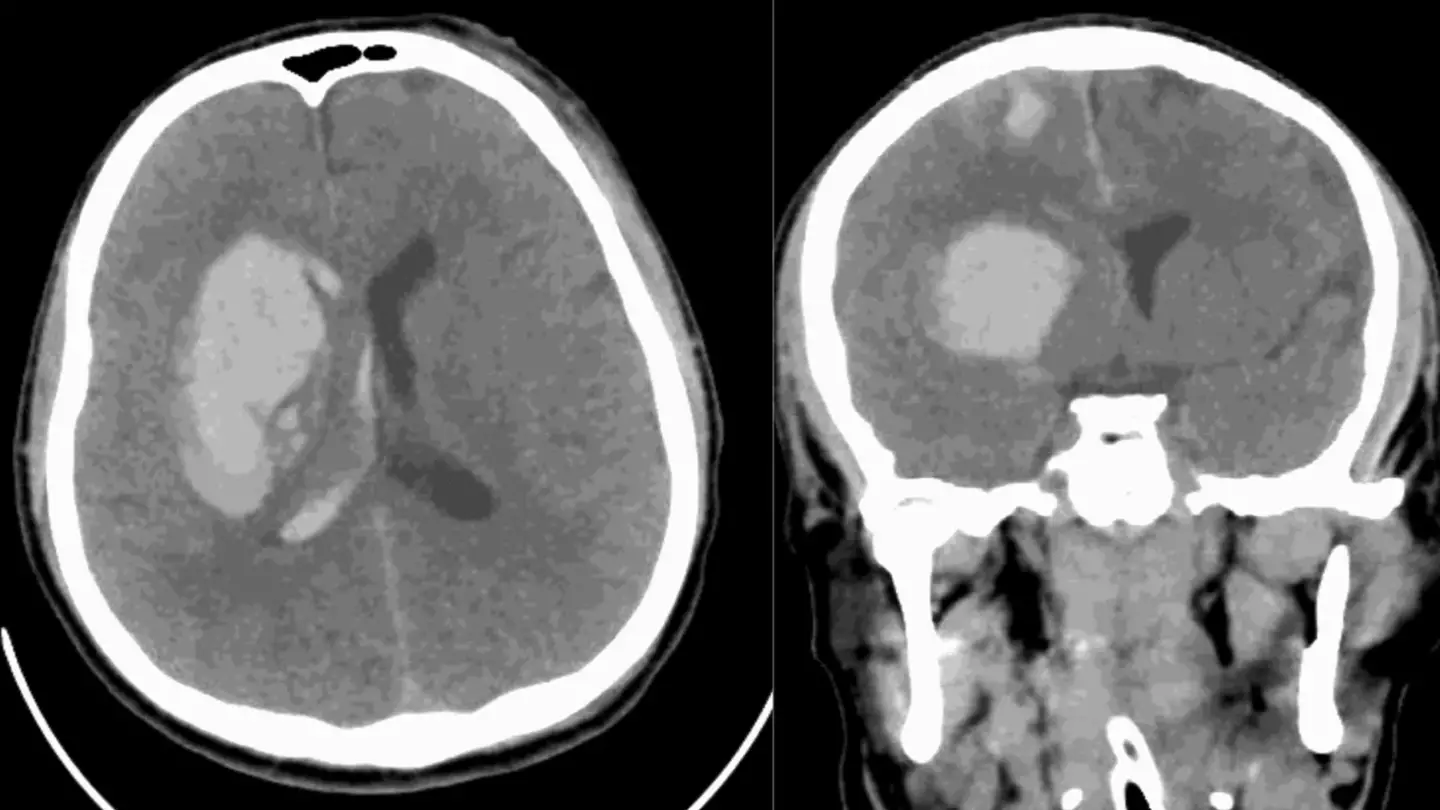

The drug-resistant fungus infected the 34-year-old just three months after suffering from a traumatic brain injury in a car crash.

He was treated in intensive care as medics dealt with bleeding from the mouth, a severe scalp laceration, and several cuts.

Part of his skull was removed to relieve pressure on his brain, but after further surgeries and antibiotic treatment, tests revealed that he had been infected with Candida auris.